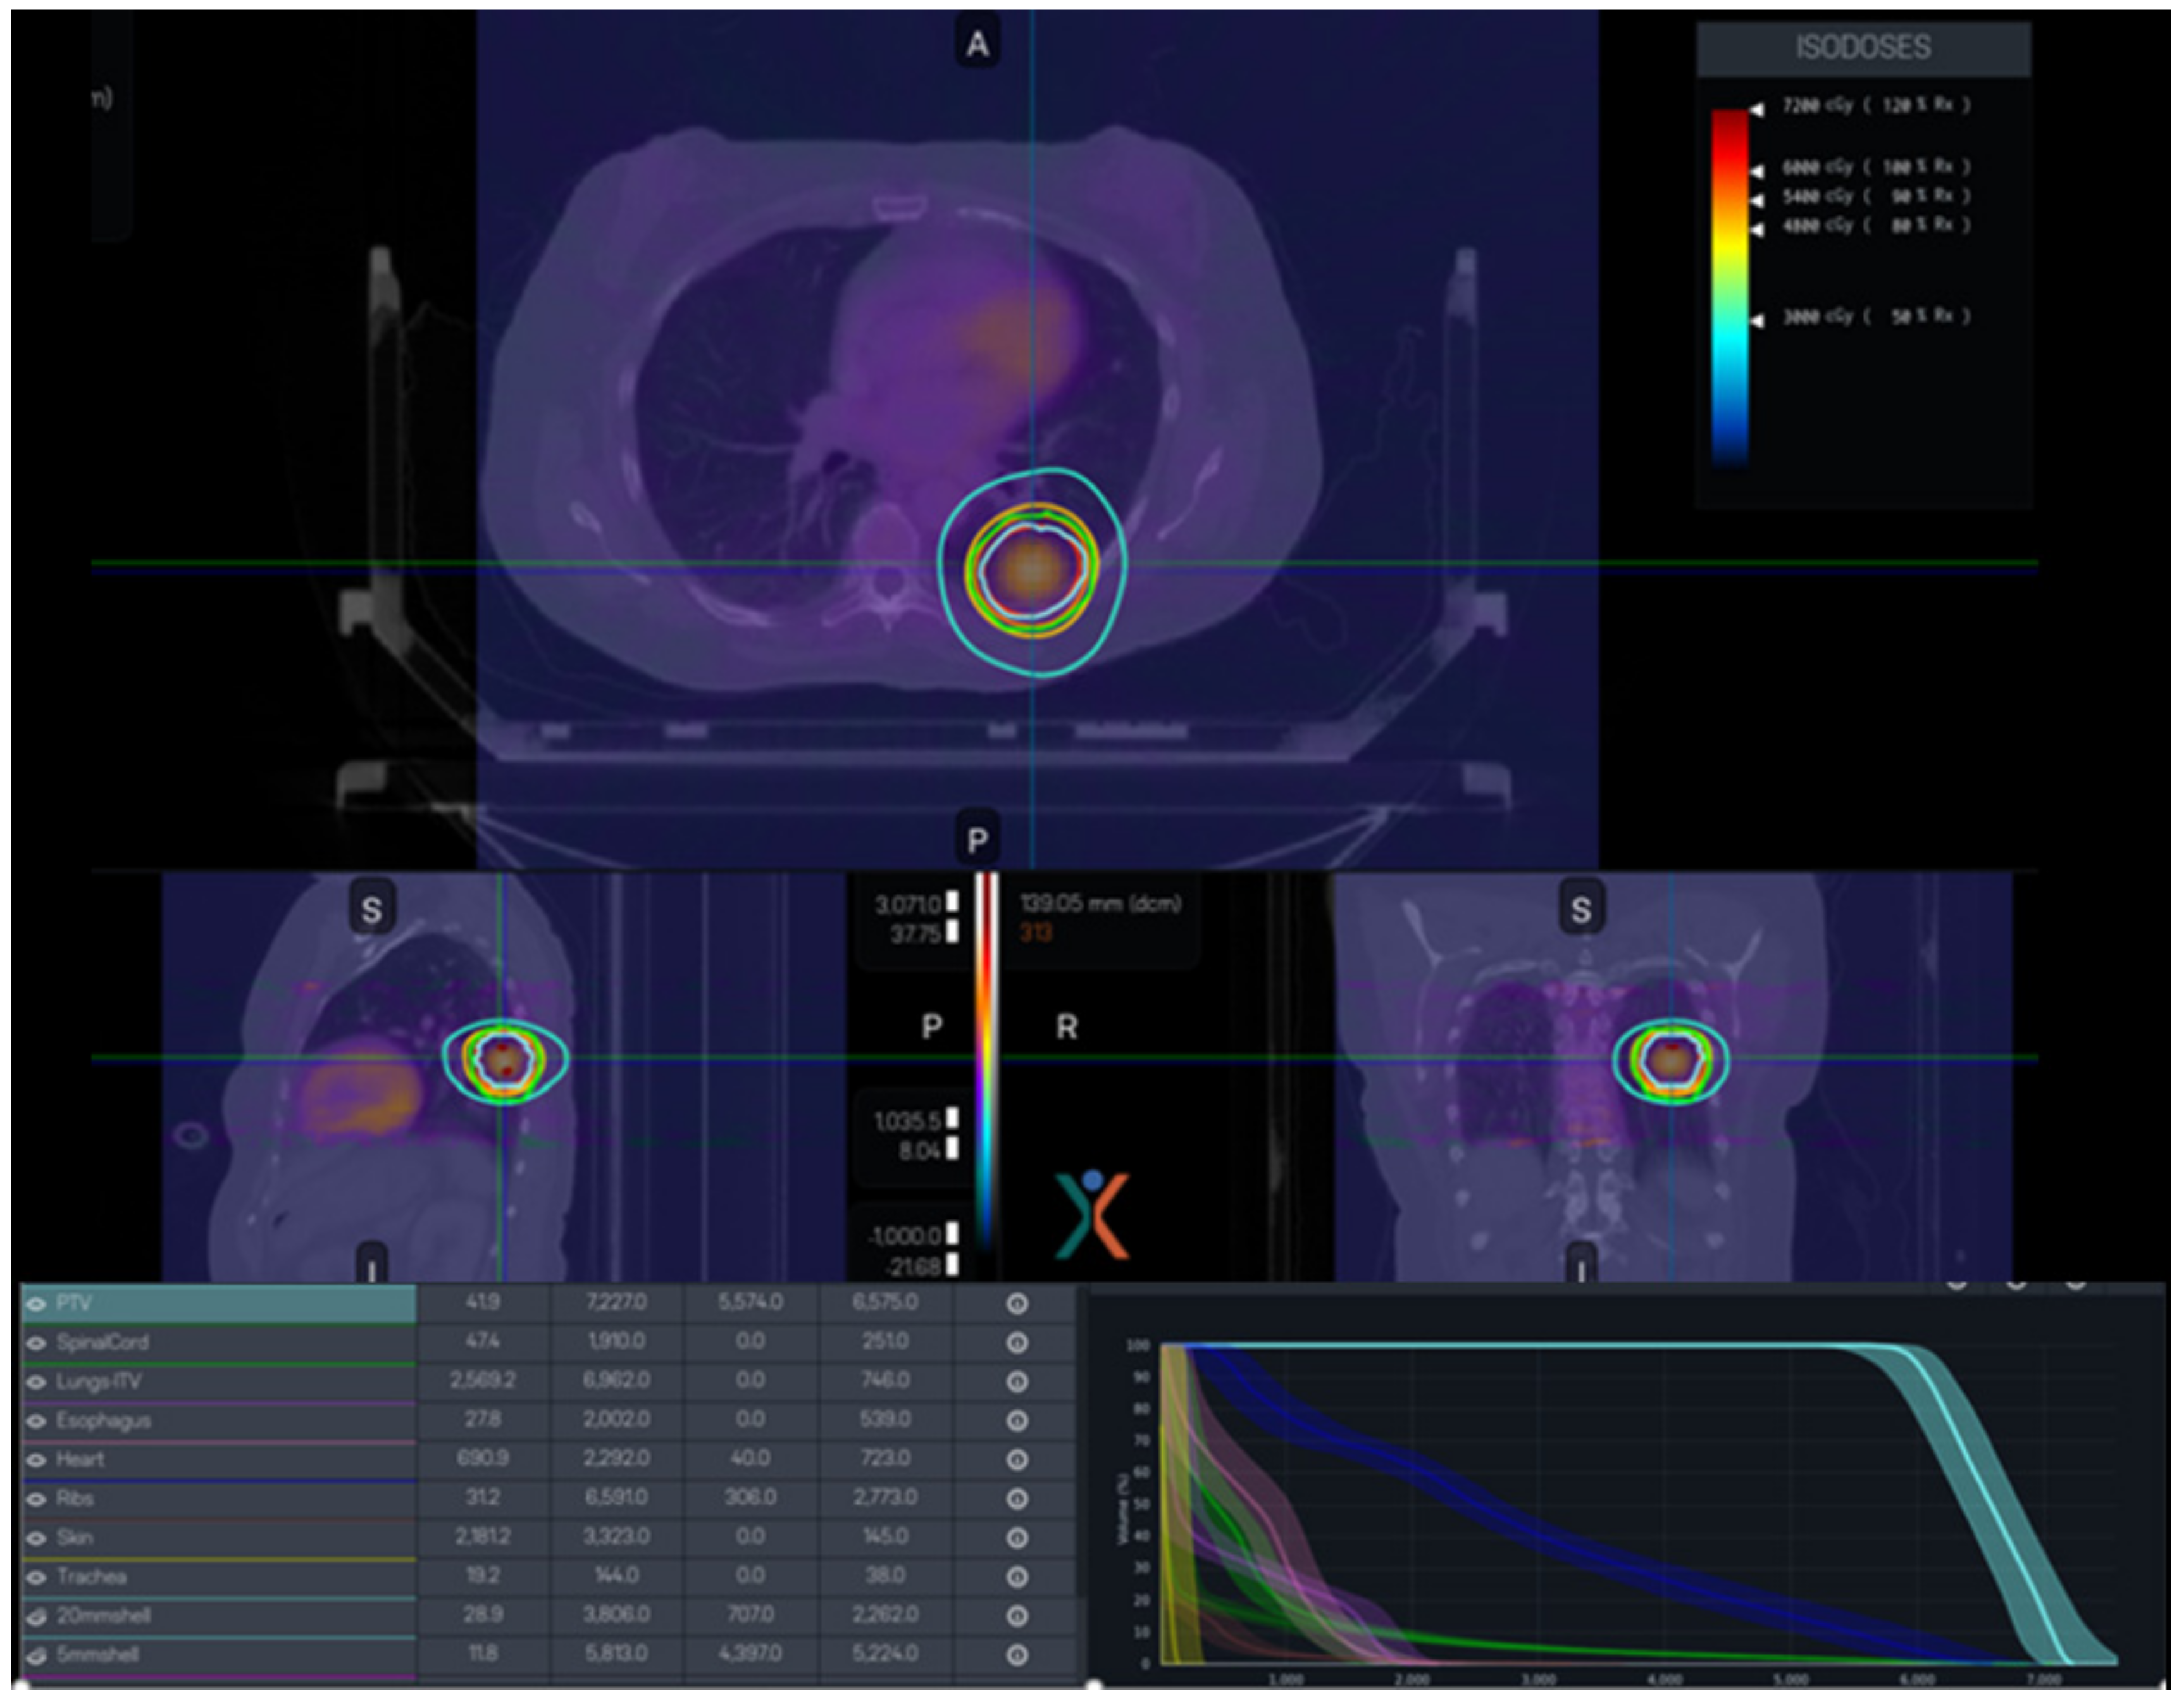

The PET-LINAC, RefleXion X1 (RefleXion Medical, Howard, CA, USA), represents a notable breakthrough in the field. It demonstrates the integration of a ring gantry LINAC and a PET-CT scanner in this groundbreaking technology, which is the first commercial implementation of PET-guided radiotherapy. The X1 system is a small radiation treatment system comprising a 6MV FFF LINAC installed on a rotating O-ring gantry that spins at a speed of 60 RPM. Additionally, there are two PET detector arrays positioned at 90-degree angles to the MV beamline. It facilitates the immediate identification and handling of molecular signals, directing the administration of radiation beams. Using this technology as a foundation, a novel therapeutic approach called SCINTIX therapy has been devised. A clinical trial conducted under an Investigational Device Exemption (IDE) has substantiated the safety and efficacy of SCINTIX therapy in the treatment of bone and lung lesions, leading to its approval by the FDA for these particular uses. Figure 6 illustrates a SCINTIX radiation plan that utilizes PET data to guide treatment for a patient with lung cancer. The optimal strategy considers both dosimetric limitations and the dispersion of PET signals. The bounded dose–volume histogram (DVH) accounts for uncertainty in both geometric and FDG intake. During the delivery process, the system continuously monitors and analyzes real-time signals, making necessary adjustments to the firing positions in order to obtain the intended dosage as per the initial design.

Figure 6.

A representative SCINTIX radiation plan specifically designed for the treatment of lung conditions.